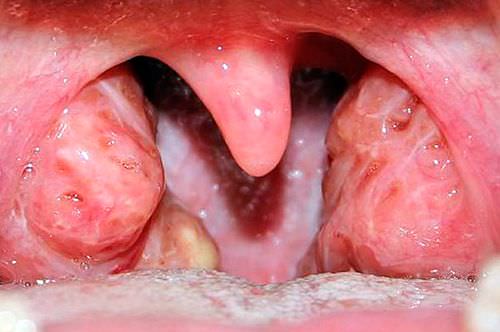

Тяжелое поражение миндалин тонзиллит

Наиболее серьезной патологией, вызванной активным размножение стрептококка или проникновением вирусов различной природы, считают ангину. Очень важно вовремя провести диагностику, чтобы исключить развитие серьезных осложнений.

В результате обычного переохлаждения иммунитет человека ослабевает, и бактерии с вирусами начинают активно осваивать новые территории. При запущенной простуде развивается тонзиллит, признаками которого являются:

- Изменение цвета миндалин на красный, увеличение их размера, разрыхление, белесый налет.

- В местах, где были ямки, на гландах можно увидеть узелки, заполненные гноем, которые вскрываются в результате регулярного полоскания.

Тонзиллит является не только следствием воспалительного процесса если присутствуют дырки в миндалинах, но и сам по себе активно способствует образованию новых углублений. Очень важно тщательно и своевременно лечить ангину для того, чтобы предотвратить такие патологии, как поражение сердца, почек, суставных и костных тканей.